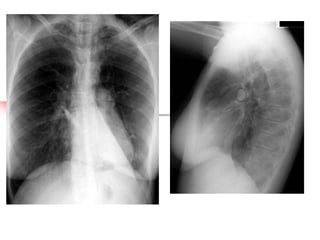

Chest X-ray Not routinely recommended in patients in the absence of:

• suspected pneumomediastinum or • failure to respond to treatment

pneumothorax

satisfactorily

• suspected consolidation

• requirement for ventilation

• life threatening asthma

81

Management of acute asthma. Thorax 2003; 58 (Suppl I): i1-i92

• 80.

Initial assessment –the role of symptoms, signs and measurements Clinical features Clinical features, symptoms and respiratory and cardiovascular signs helpful in recognising severe asthma, but none specific, and their absence does not exclude a severe attack PEF or FEV1 Measurements of airway calibre improve recognition of severity and guide hospital or at home management decisions. PEF is more convenient and cheaper than FEV1. PEF as % previous best value or % predicted most useful Pulse oximetry Necessary to determine adequacy of oxygen therapy and need for arterial blood gas measurement. Aim of oxygen therapy is to maintain SpO 2 92% Blood gases (ABG) Necessary for patients with SpO2 <92% or other features of life threatening asthma Chest X-ray Not routinely recommended in patients in the absence of: • suspected pneumomediastinum or • failure to respond to treatment pneumothorax satisfactorily • suspected consolidation • requirement for ventilation • life threatening asthma 81 Management of acute asthma. Thorax 2003; 58 (Suppl I): i1-i92

• 81.

Initial assessment –the role of symptoms, signs and measurements Clinical features PEF or FEV1 Measurements of airway calibre improve recognition of severity and guide hospital or at home management decisions. PEF is more convenient and cheaper than FEV1. PEF as % previous best value or % predicted most useful Pulse oximetry Necessary to determine adequacy of oxygen therapy and need for arterial blood gas measurement. Aim of oxygen therapy is to maintain SpO 2 92% Blood gases (ABG) Necessary for patients with SpO2 <92% or other features of life threatening asthma Chest X-ray Not routinely recommended in patients in the absence of: suspected pneumomediastinum or • failure to respond to treatment • pneumothorax satisfactorily suspected consolidation • requirement for ventilation • life threatening asthma • Systolic paradox 82 Clinical features, symptoms and respiratory and cardiovascular signs helpful in recognising severe asthma, but none specific, and their absence does not exclude a severe attack Abandoned as an indicator of the severity of an attack Management of acute asthma. Thorax 2012